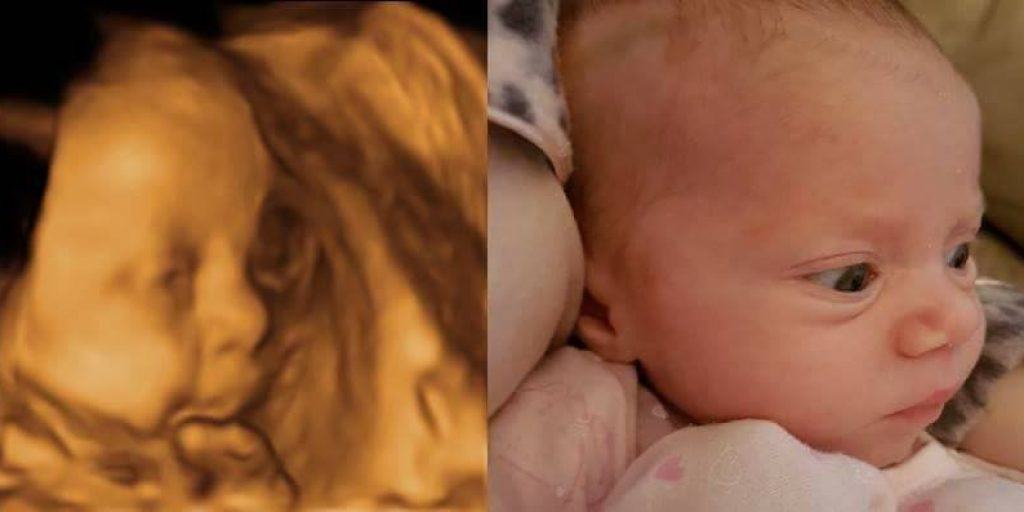

When I was pregnant with Autumn, Dave and I were umming and ahing over whether or not to have a 4D scan. When my Mum said she’d found a voucher for Window to the Womb in Bexleyheath on Groupon and that she’d pay half of it, we decided to go for it. We booked it it when I was 32 weeks + 2 days pregnant and thoroughly enjoyed the experience.